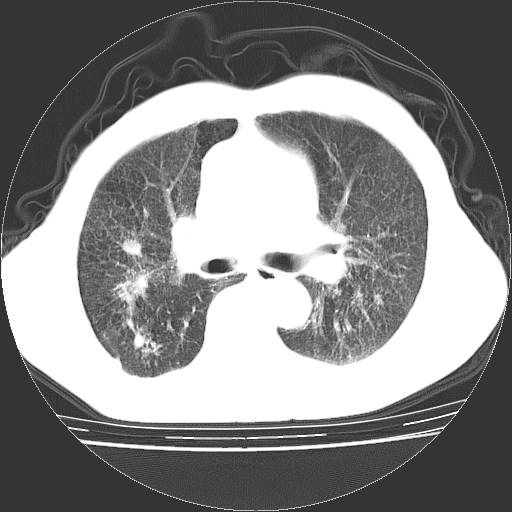

男,72岁,反复咳嗽、憋气一年余,有15年的煤矿井下工作史。

两上肺为主的大小不等结节影伴广泛纤维化,结合病史考虑尘肺。

1、双肺中上叶结节影结合病史考虑巨块型矽肺结节。

2、慢支炎并肺气肿

3、双下肺纤维化灶并左下肺局限性肺气肿。

支持 尘肺,肺心病?-------15年的煤矿井下工作史,双上肺叫对称的片团结节影,内见斑状钙化,边缘见粗长毛刺影,肺纹理混乱,可见网状及磨玻璃样影,肺门纵膈见多个淋巴结钙化